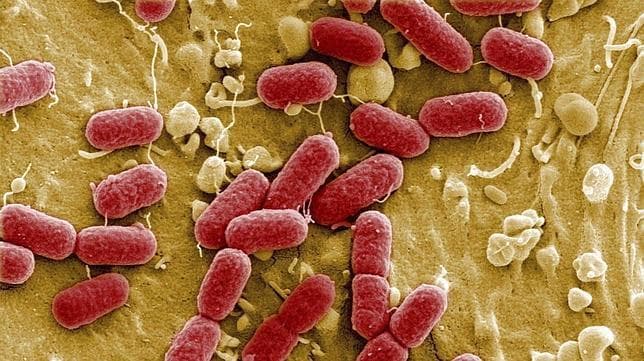

Escherichia Coli

Escherichia coli es la especie tipo del género Escherichia, que a su vez, es el genero tipo de la familia Entereobacteriaceae.

Bacillus cereus

El Bacillus cereus se presenta en forma de células vegetativas de gran tamaño que constituyen cadenas; es anaerobio facultativo,